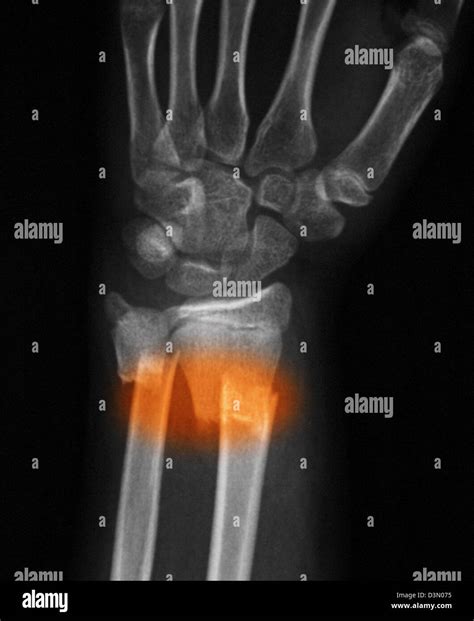

• X-Rays: X-rays are the primary imaging tool used to confirm the presence and severity of a fracture. They provide detailed images of the bones and can show the exact location and type of fracture.

• Deformity: The forearm may appear deformed or bent at an unusual angle.